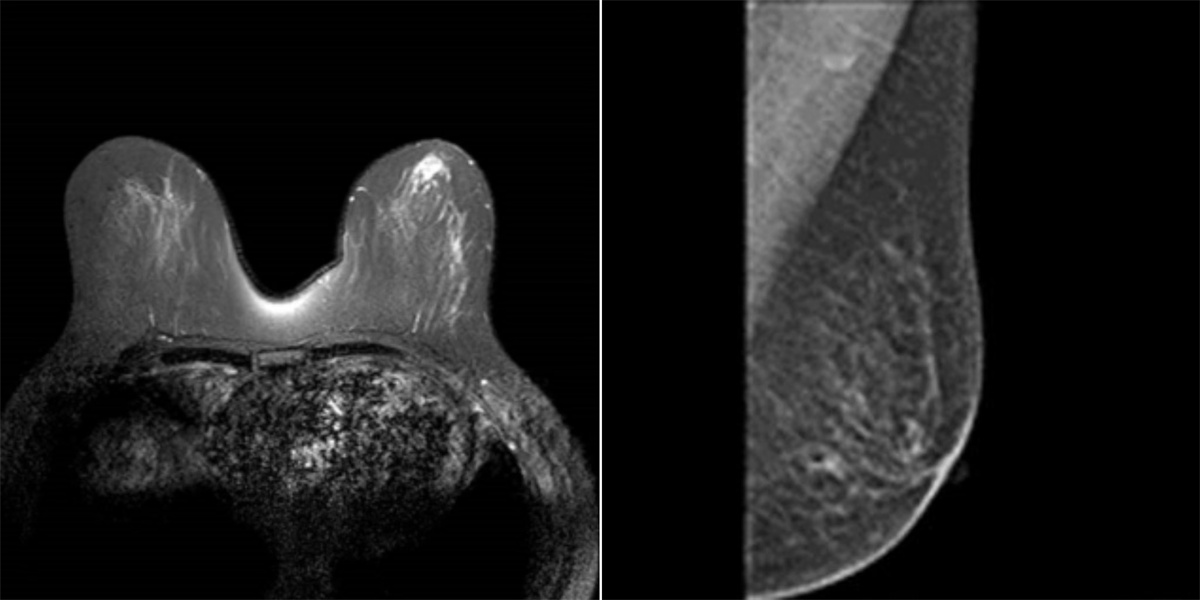

近日,色情导航 乳腺外一科副主任崔舜瑀教授团队成功施行东北三省首例达芬奇机器人下经腋窝单孔全腔镜乳腺癌改良根治术。标志着色情导航乳腺外科进入达芬奇机器人高端精准新时代,为更多乳腺患者带来了新的希望。

67岁的患者郭女士,因“右乳肿物”入院。经查双乳房表面皮肤无红肿破溃,无卫星结节,右侧乳房有2个肿物分别与不同象限,2x2cm,两个乳腺肿物均是恶性肿瘤。根据CACA-CBCS(2022版)指南、以及考虑患者本身年龄及病情,不适合保留乳房手术。但郭女士对切口的长度及位置有强烈的要求及意愿。经乳腺外一科团队会诊,并与家属充分沟通后,最终选择此术式。

52岁的患者佟女士,因“左乳肿物”入院。经查双乳房表面皮肤无红肿破溃,无卫星结节,左侧乳房肿物2x2cm。腋下淋巴结肿大融合2x2cm,给予系统治疗后。此次入院检查适合手术。根据CACA-CBCS(2022版)指南、以及考虑患者本身年龄及病情,不适合保留乳房手术。

崔舜瑀教授带领团队在术前进行了充分的病情分析、术前切口的标记与测量,依照两位女士的意愿,为她们量身定制了个性化的手术方式和预案准备。术中,团队使用自制的“乳腺单孔腔内镜戳卡”进行操作,1例采用“逐层法”切除全部腺体并完整保留乳头乳晕。1例采用“逐层法”切除全部腺体及乳头乳晕,手术过程十分顺利。目前患者切口愈合良好,术区无任何异常,无不良反应及并发症,此术式在避免术后放疗的同时,兼顾健康和美观,且“无痕”,患者及家属表示非常满意,并顺利出院。

术后,崔舜瑀教授表示,该术式的主要亮点一是通过达芬奇机器人灵活的机器手及超清晰3D成像技术达到更精细的手术操作,既能解决肿瘤治疗又能最大限度减少损害,满足患者对健康和美的双重需求;二是应用前哨淋巴结活检切口施行单孔建腔使其切口更加隐蔽,解决了乳房表面切口带来的皮瓣坏死、积液等术后并发症的风险,规避了患者胀痛不适等缺点,实现了乳房表面无痕化的美容效果,而且保留胸大肌的功能不受影响,改善乳房形态。